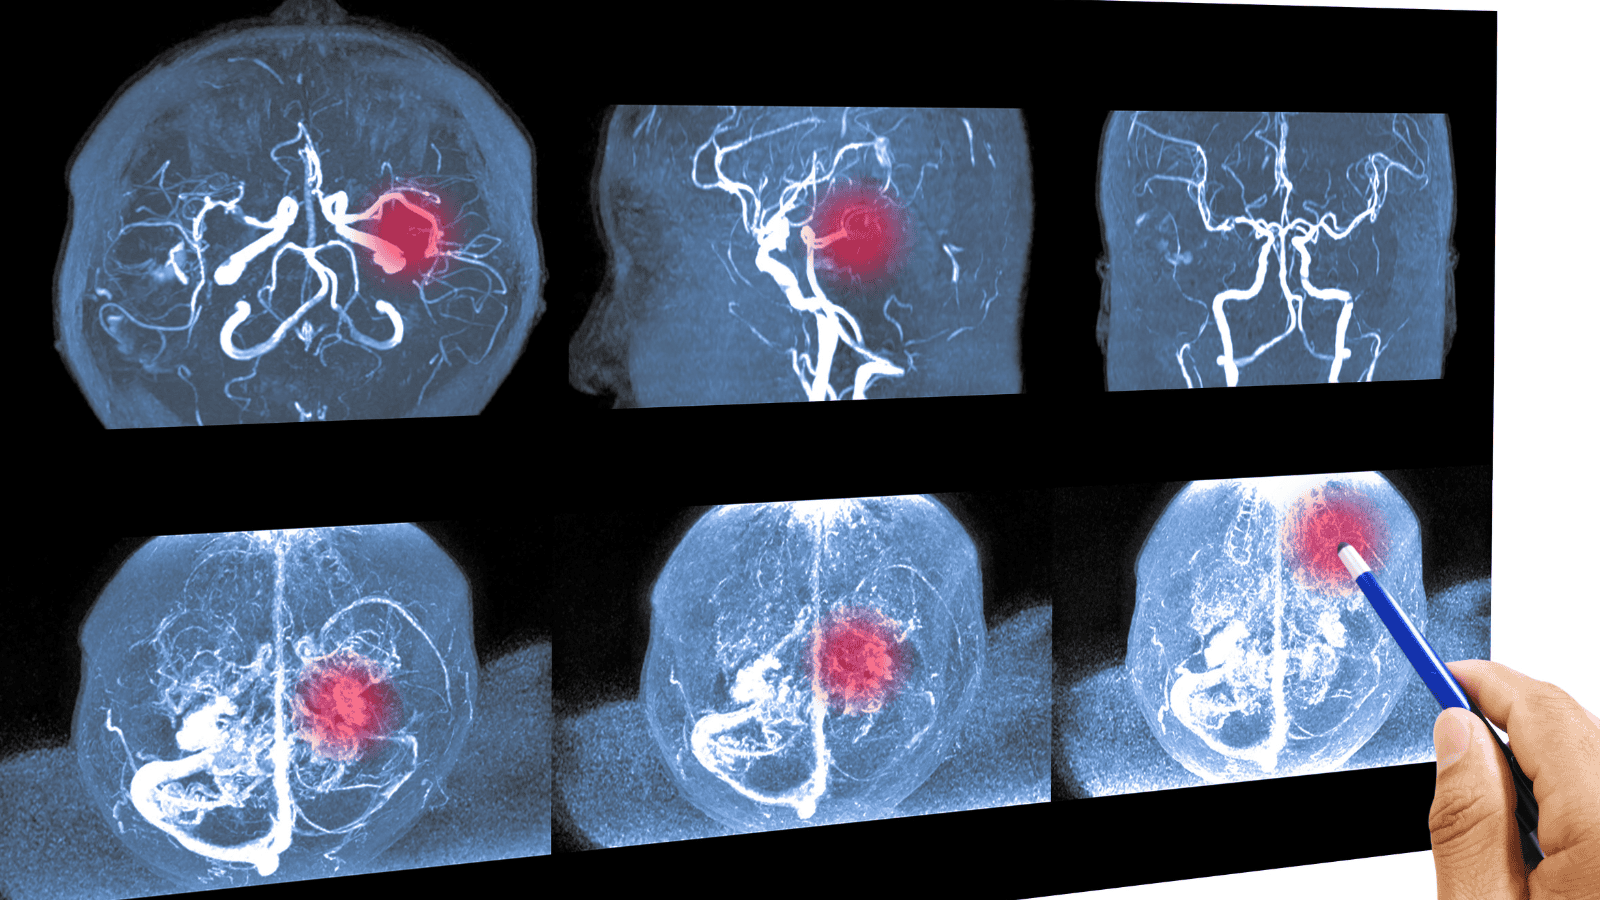

Tętniak - jak go rozpoznać?, fot. Tonpor Kasa/Getty Images

Tętniak to patologiczne poszerzenie światła naczynia krwionośnego (tętnicy), wynikające z osłabienia jego ściany. Można go porównać do balonu tworzącego się na dętce rowerowej – im cieńsza staje się ściana, tym większe ryzyko jej przerwania pod wpływem ciśnienia krwi. Tętniaki najczęściej lokalizują się w aorcie (największej tętnicy organizmu) oraz w naczyniach mózgowych (tętnice koła tętniczego Willisa).

Kiedy do lekarza w trybie planowym? Skonsultuj się ze specjalistą, jeśli w Twojej rodzinie występowały przypadki tętniaków lub nagłych zgonów sercowych w młodym wieku. Lekarz może zlecić badania obrazowe (np. angio-TK lub angio-rezonans), które pozwolą wykryć „bombę”, zanim dojdzie do tragedii.